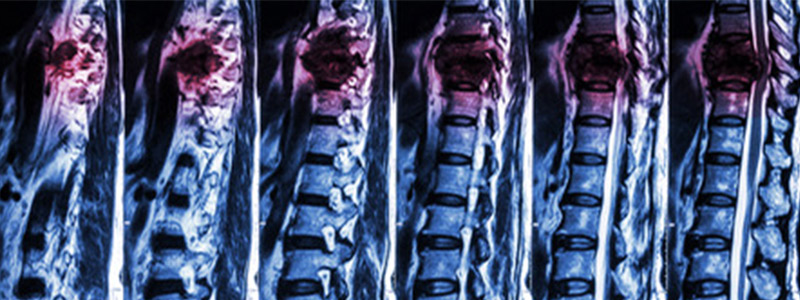

Sus hallazgos, publicados en la revista 'Nature', se basan en una investigación que ya ha permitido que varios parapléjicos vuelvan a caminar mediante la estimulación eléctrica epidural (EEE). No obstante, en lugar de apuntar a la región de la médula espinal que produce los movimientos de las piernas, administraron EES en la región que contiene los circuitos neurales que regulan la presión arterial.

Además, adaptaron el protocolo de estimulación en tiempo real en base a las medidas tomadas por un tensiómetro implantado en una arteria. El monitor mide la presión arterial de forma continua y adapta las instrucciones enviadas a un marcapasos que, a su vez, emite pulsos eléctricos sobre la médula espinal. La estimulación es biomimética, ya que recapitula la activación natural del sistema hemodinámico del organismo.